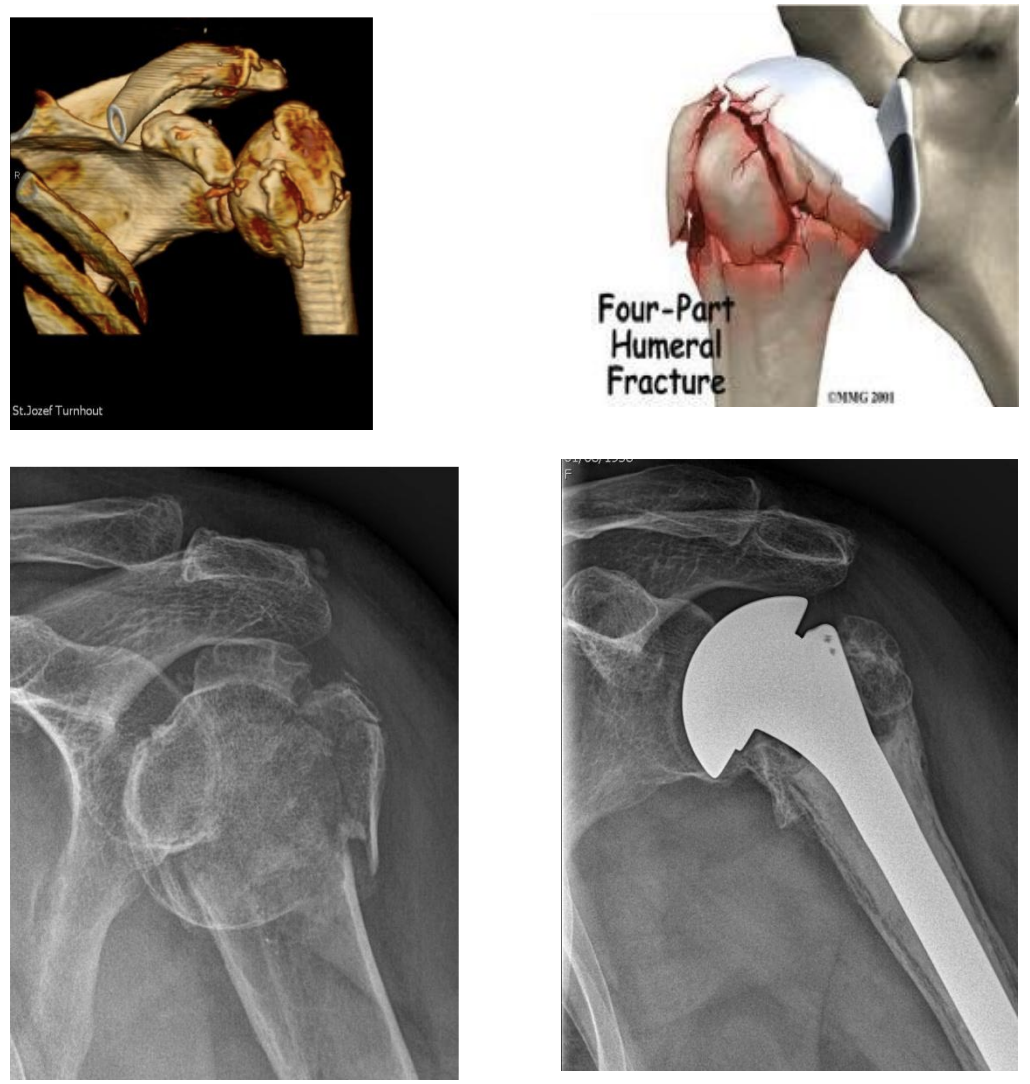

- Na complexe breuken van de schouder.

Fractuur prothese (C)

Prothese dewelke gebruikt wordt bij breuken van de schouderkop.